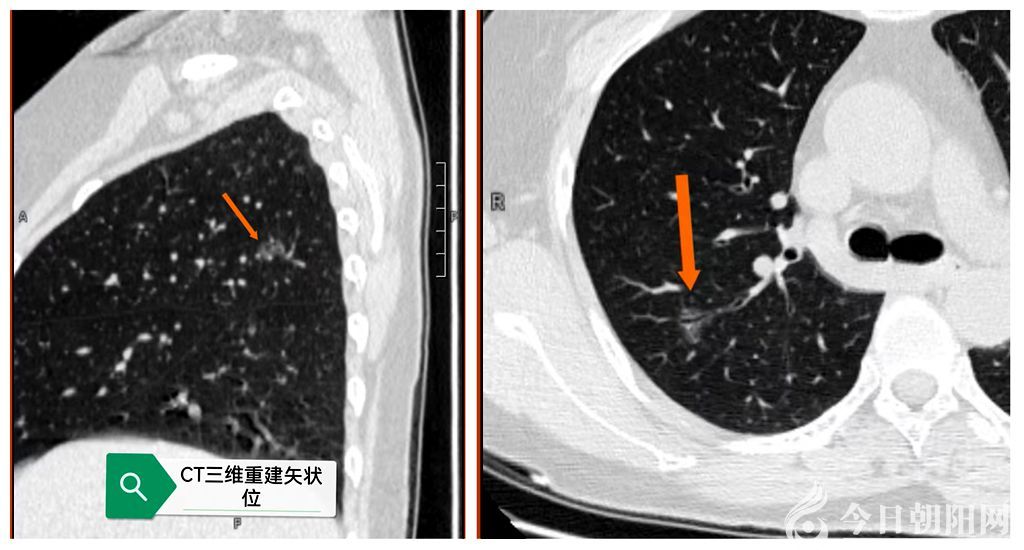

王女士于1年前發(fā)現(xiàn)多發(fā)肺結(jié)節(jié)后進(jìn)行多次復(fù)查,其中右肺上葉最大徑12毫米的磨玻璃結(jié)節(jié)有增大趨勢。她曾在多家醫(yī)院求醫(yī)問診,有的醫(yī)生建議手術(shù)切除,有的醫(yī)生建議保守觀察,再加上對手術(shù)損傷及后遺癥的懼怕,王女士非常焦慮,手術(shù)還是觀察,一直猶豫不決。

就在這時,她的同鄉(xiāng)李先生也是因?yàn)榉谓Y(jié)節(jié)遠(yuǎn)道來到朝陽市第四醫(yī)院尋醫(yī)問診,并在此醫(yī)院外科接受了單孔無管胸腔鏡手術(shù),術(shù)后快速康復(fù),第三天已經(jīng)和朋友自駕車從朝陽回到了吉林家里。李先生向王女士介紹,他做的是全麻保留自主呼吸單孔無管胸腔鏡手術(shù),這是一種屬于目前國際先進(jìn)水平的外科技術(shù),手術(shù)過程中不需要插尿管、不需要插氣管插管麻醉、術(shù)后也沒有胸腔引流管,僅僅通過一個幾厘米微小切口完成手術(shù),術(shù)后痛苦輕,并且恢復(fù)特別快,他手術(shù)結(jié)束后很快就清醒了,是自己從手術(shù)床移動到轉(zhuǎn)運(yùn)床上回到病房的,術(shù)后6個小時就能自己下地活動了。王女士聽到李先生的介紹,并且親眼看到李先生手術(shù)后快速康復(fù)的狀態(tài),果斷決定到朝陽市第四醫(yī)院外科手術(shù)。王女士經(jīng)過李先生引薦馬上聯(lián)系上了市第四醫(yī)院院長、外科主任張瑛,表達(dá)了自己強(qiáng)烈的手術(shù)意愿。張瑛通過線上閱片后也認(rèn)為王女士右肺上葉后段磨玻璃結(jié)節(jié)有手術(shù)適應(yīng)癥,同意了她的請求,并約定了手術(shù)時間。于是第二天王女士在家人陪同下乘坐高鐵如約來到市第四醫(yī)院就診。在市第四醫(yī)院外科團(tuán)隊(duì)的周到安排下,王女士如愿以償如期按照計(jì)劃順利實(shí)施了手術(shù)。按照既定方案,病人自主呼吸麻醉下,醫(yī)生通過一個3cm的切口,約用50分鐘將右肺上葉結(jié)節(jié)切除,并進(jìn)行了淋巴結(jié)采樣。術(shù)中病人一切良好,術(shù)后約10分鐘患者就已清醒,并回到病房,而且很快就恢復(fù)了飲水進(jìn)食,術(shù)后6小時下地活動,術(shù)后第二天復(fù)查胸片胸腔內(nèi)情況良好,醫(yī)生就建議她可以出院了。更為幸運(yùn)的是,王女士術(shù)后病理診斷為:肺微浸潤腺癌,貼壁生長95%,乳頭5%,無淋巴結(jié)轉(zhuǎn)移。這樣的病理結(jié)果意味著她的腫瘤磨玻璃結(jié)節(jié)剛剛從良性向惡性發(fā)展,手術(shù)切除是最佳手術(shù)時機(jī),切除也就意味著治愈了。